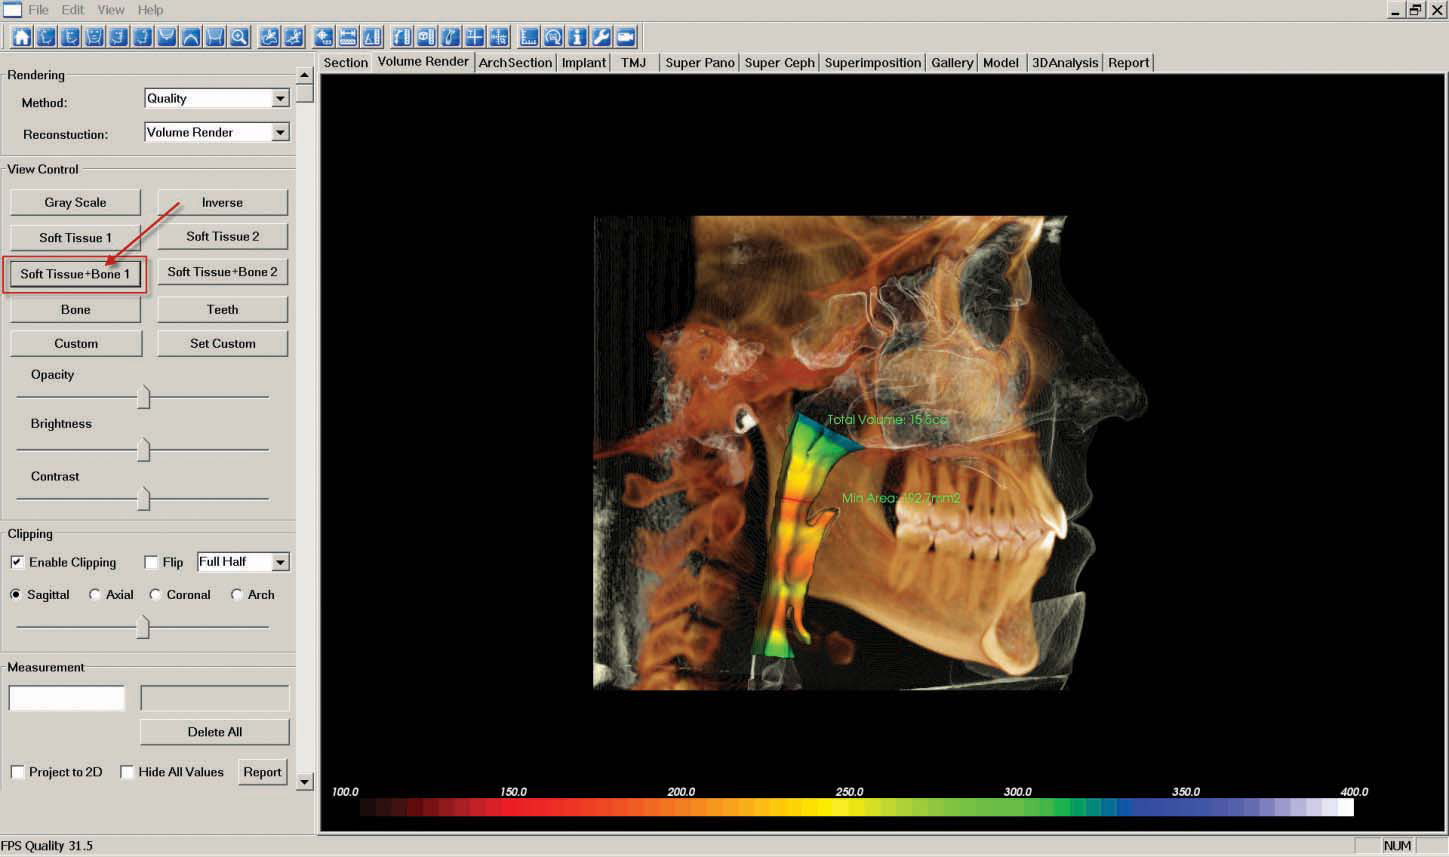

j. The "Airway" image is created in the "Volume Render" tab by selecting the "Airway Measurement" icon at the top of the screen and choosing "Volume Render" from the "Reconstruction" drop-down menu located in the upper left corner of the screen.

The skull will automatically orient for optimum airway marking. To begin measuring, begin at the base of the airway and click inside the airway passage to place several points moving upward. Right click to finish at the height the doctor determines should be used for every patient when measuring airway.

You might then want to switch from the "Gray Scale" view to the "Soft Tissue + Bone 1" view using the icons on the left side of the screen.

As described in step 7, "Capture to Gallery" and name the image "Airway."